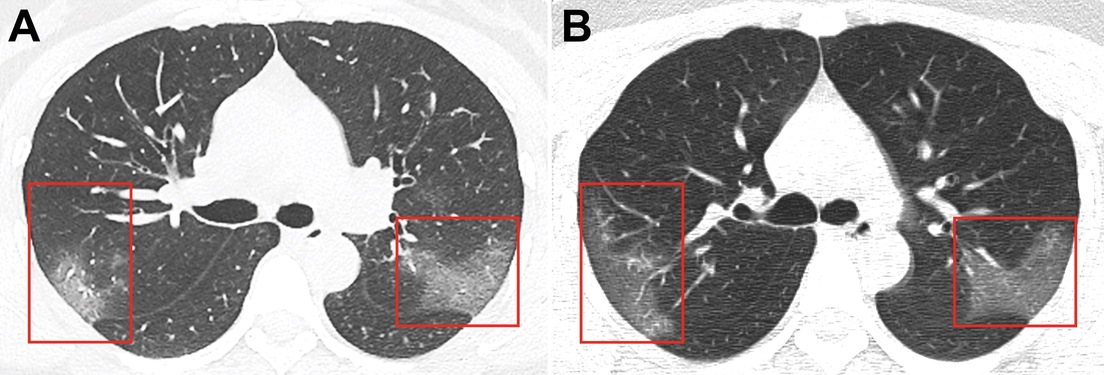

A través de las radiografías, los médicos observaron unas manchas blancas en la esquina inferior de sus pulmones, llamadas por los especialistas como la "opacidad de vidrio esmerilado".

El radiólogo de la Universidad Thomas Jefferson (EE.UU.), Paras Lakhani —que no participó en el estudio, pero examinó las imágenes—, explicó que son habituales en pacientes enfermos de neumonía común y muestran la presencia de líquido en los espacios pulmonares. No obstante, especificó que no son un síntoma claro para diagnosticar el nuevo coronavirus en un paciente, informa Business Insider.

Pero en este caso, los investigadores detectaron que las manchas se extendían hasta los bordes de los pulmones de la mujer, una característica que también se había detectado en los pacientes con SARS y MERS. Lakhani indicó que en las imágenes detectaron que el nuevo brote tiene "muchas características similares" con las otras dos epidemias.

Para descartar que no se tratara de una neumonía, los especialistas repitieron las radiografías al cabo de 3 días, cuando la paciente ya había recibido su tratamiento, y descubrieron que las manchas blancas se habían vuelto más extensas y pronunciadas.